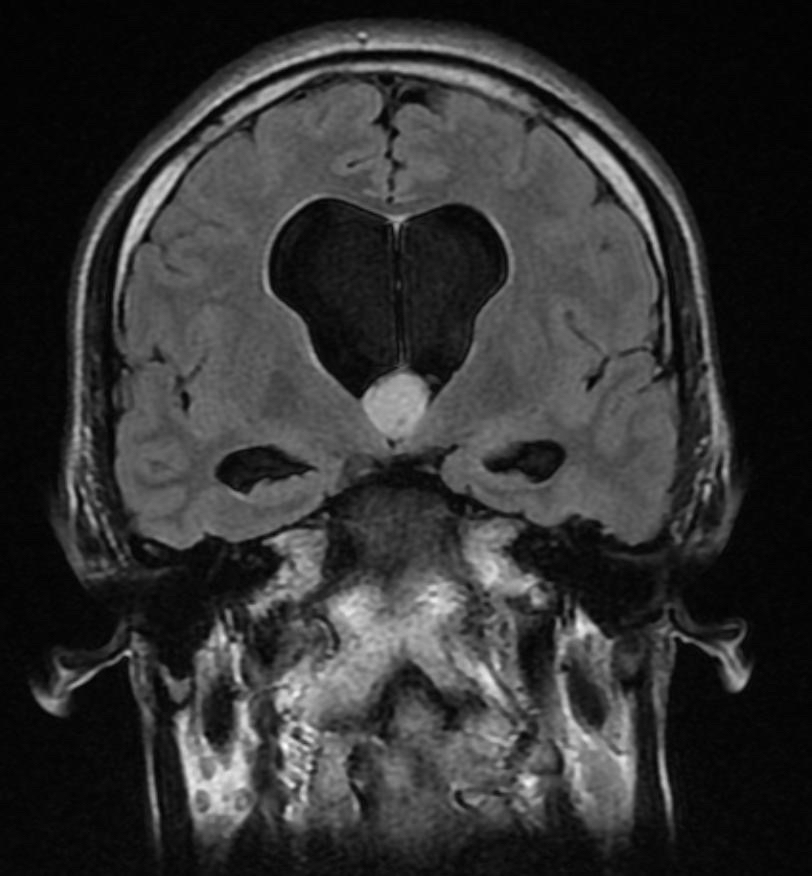

تم تنفيذ العملية النوعية باستخدام المنظار الجراحي لاستئصال كيس غرواني عميق، مما أعاد الأمل للمريض الذي كان يعاني من صداع شديد وقيء متكرر لأكثر من شهر.

وأكدت الأشعة بعد العملية استئصال الكيس بشكل كامل، وعدم وجود أي نزيف أو مضاعفات، مع تحسن ملحوظ في حالة الاستسقاء الدماغي.

والكيس الغرواني عبارة عن كيس يحوي مادة جلاتينية في موقع حساس حيث يسد مجرى تصريف السائل الدماغي في الدماغ، مما يسبب الاستسقاء الدماغي وارتفاع ضغط الدماغ، وقد يتسبب بالوفاة المفاجئة لا سمح الله في نسبة 3 - 35% في بعض التقارير الطبية.